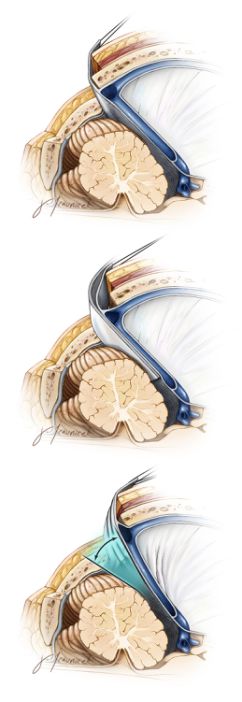

图11. 传统颅骨和硬脑膜切开方法限制了医生的工作角度,同样限制了小脑上入路的显露空间(上图)。放置固定牵开器切开小脑幕,尽管可以抬起横窦,但是不能明显扩大手术视野,事实上,它可能还会影响到手术的工作角度(中图)。小脑幕上缝线并牵拉、抬起小脑幕,并可以抬起横窦,扩大手术视角(下图)。